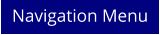

Aufhebung von Geldrollenbildung im Blut

Aufhebung von Geldrollenbildung im Blut

Aufhebung von Geldrollenbildung im Blut